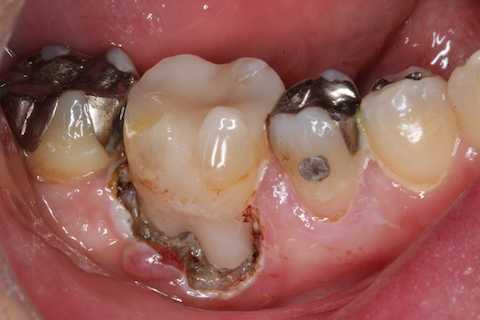

残根上のCR8 2025.10.28